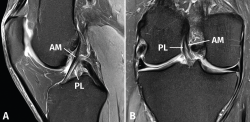

Figura 2. Anatomía normal del ligamento cruzado anterior (LCA) en secuencias convencionales de resonancia magnética (RM). A: corte sagital potenciado en densidad protónica (DP) con supresión grasa que muestra en toda su extensión el trayecto del fascículo anteromedial (AM); B: corte coronal de RM potenciado en DP con supresión grasa que muestra la anatomía bifascicular. PL: fascículo posterolateral.